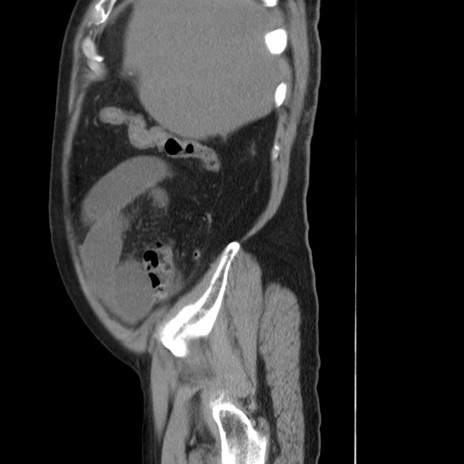

症例20(矢状断像)

【症例】 60歳代男性

【主訴】 腹部膨満、嘔吐

【現病歴】5日前頃より倦怠感を認め食事量減少し4日前の朝嘔吐、食事摂取困難となった。 3日前近医受診し点滴施行され整腸剤などを処方された。 当日他院を受診し、腹部膨満著明、炎症反応の上昇(CRP10.8、WBC11200)あり、紹介受診となる。

【身体所見】 意識JCS1 受け答えがはっきりしないBP 111/57mHg、 P 67bpm、、BT35.2°C、SpO2 97%(RA)、 腹部:膨隆、打診で鼓音あり、全体的に圧痛有り、腸蠕動音(-)、反跳痛ははっきりせず。

【データ】WBC 11400、CRP 14.20